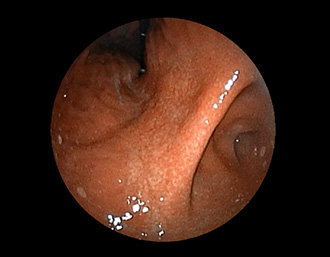

症例1:胃潰瘍(37才、男性)

①胃潰瘍(Stage A1)

健診:胃レントゲン検査で、胃角部ニッシェを指摘され当院受診。

胃角部小弯に、深くて大きな、大きさ約10mmの胃潰瘍(stage 1)があり、潰瘍底は一部白苔はみ出しを認める。エソメプラゾールマグネシウム水和物投薬で治療開始しました。